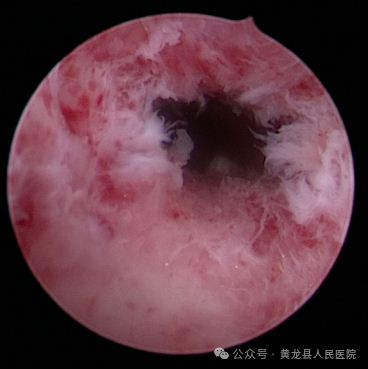

宫腔镜子宫内膜赘生物切除术。

患者刘某,51岁,不规则阴道出血11天。术中见子宫内膜厚,不平整,可见多个指状突起,大小约0.2-0.4cm,双侧输卵管开口可见,确定手术方案,经患者同意后,行宫腔镜子宫内膜赘生物切除术。术后病检:子宫内膜息肉。